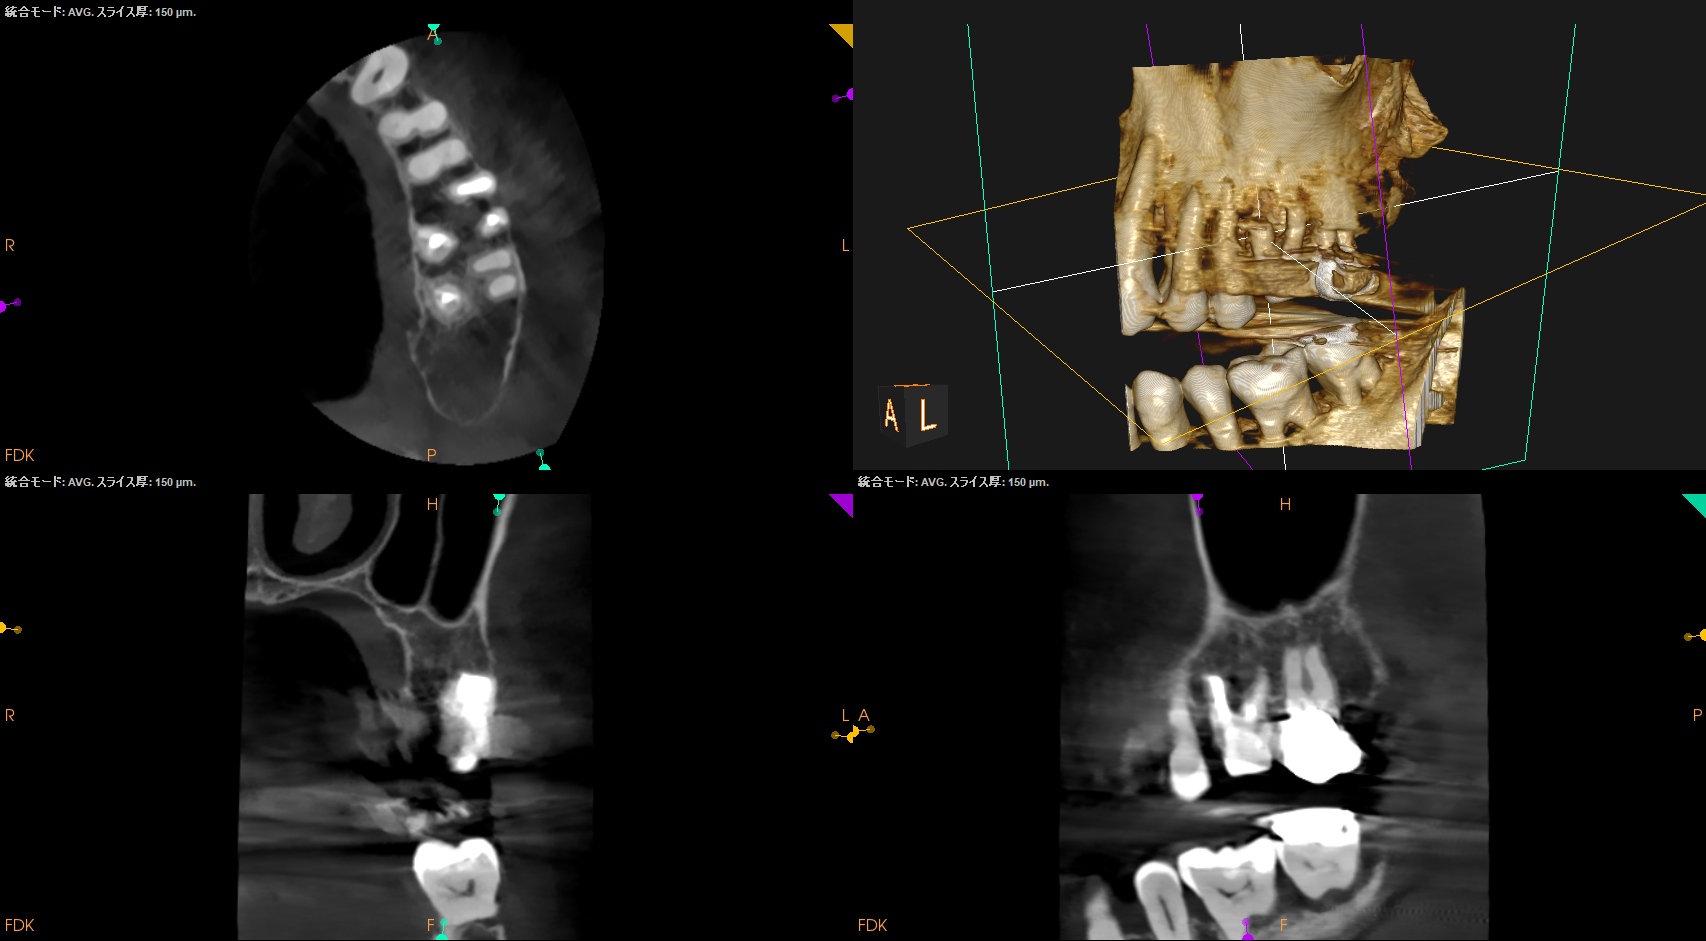

#14 Post-op 2yr recall(2026.4.19)

初診時と比較した。

歯槽骨の欠損は完治した。

術前の臨床症状も消失した。